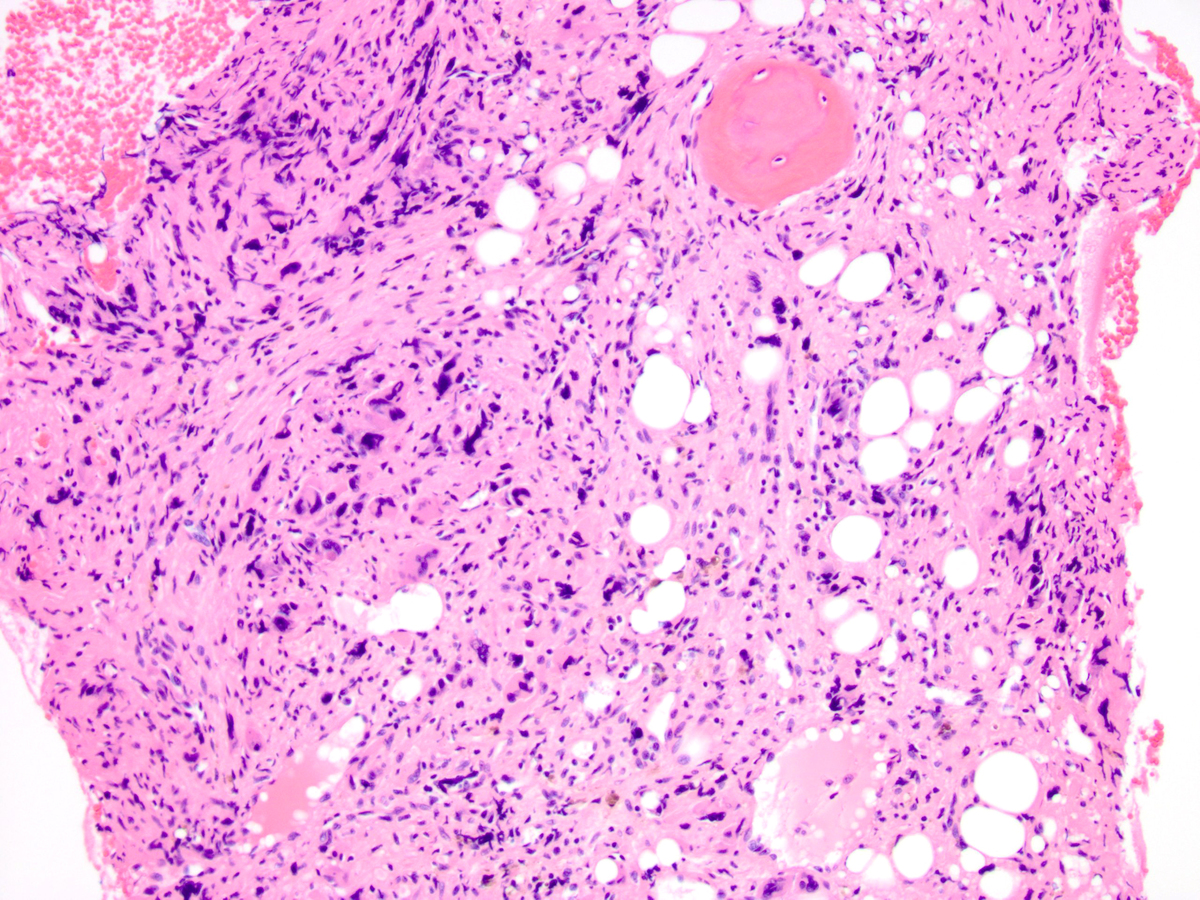

| Other areas are more cellular and contain an increased number of atypical megakaryocytes | ![]() |

| A high-power image shows a marked megakaryocytic proliferation with abnormal-appearing megakaryocytes, micromegakaryocytes and megakaryoblasts. Normal maturing hematopoiesis is virtually absent. | ![]() |